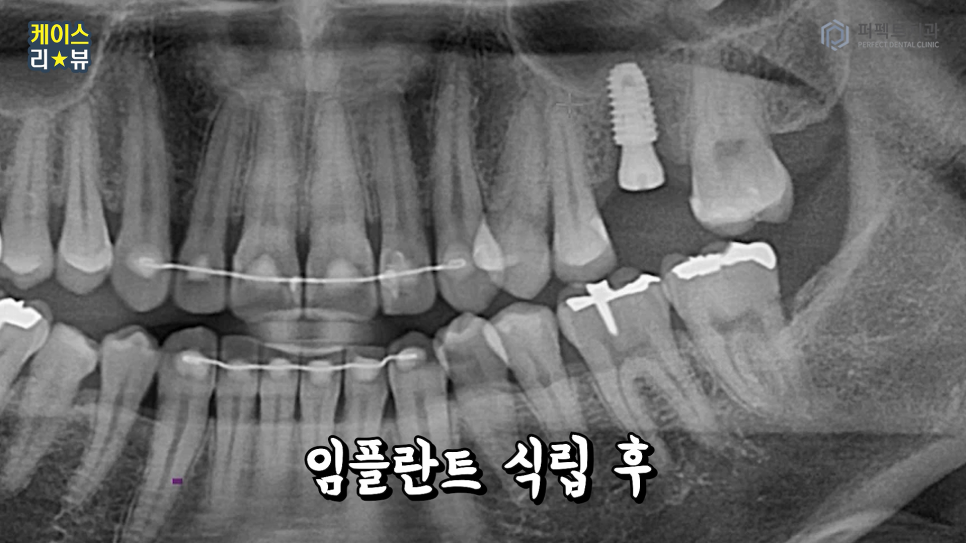

3분만에 임플란트를 식립한 결과도 한 번 볼게요.

네, 원하는 위치에 잘 자리를 잡았습니다.

뼈이식 후 식립을 한 경우가 되었는데

임플란트 식립하는 과정은 약 3분정도 소요되었습니다.